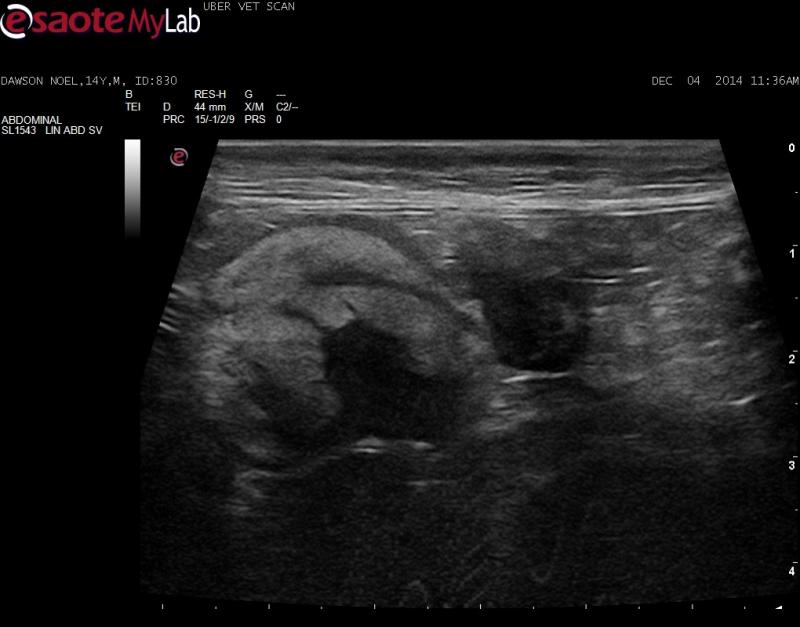

– in the mid-abdomen there is a hyperechoic structure with an unusual appearance that I am having trouble identifying

Is this neoplastic omentum? Big ugly LN? Something else?

Given the echotexture and

Given the echotexture and position and looks like the mesenteric artery in the middle IM betting on fibrosarc infiltrated mesenteric LN. Likely need to core bx to get the dx because fibrosarc tough to exfoliate on fna… maybe an 18g.

I agree with Eric. Likely

I agree with Eric. Likely mets to the mesenteric lymph nodes. Will take agressive needling while applying negative pressure to the syringe while stabbing to get cells. Usually I get results on these kinds of lesions with this technique.